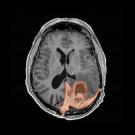

Showcasing Art that Celebrates Creativity and Healing Amid Cancer

They aren’t professional artists, and to have their work featured by a major metropolitan museum seemed unfathomable. They’d been diagnosed with a gamut of cancers including brain cancer, breast cancer, multiple myeloma, colon, ovarian cancer. Some were diagnosed many years ago, others as recently